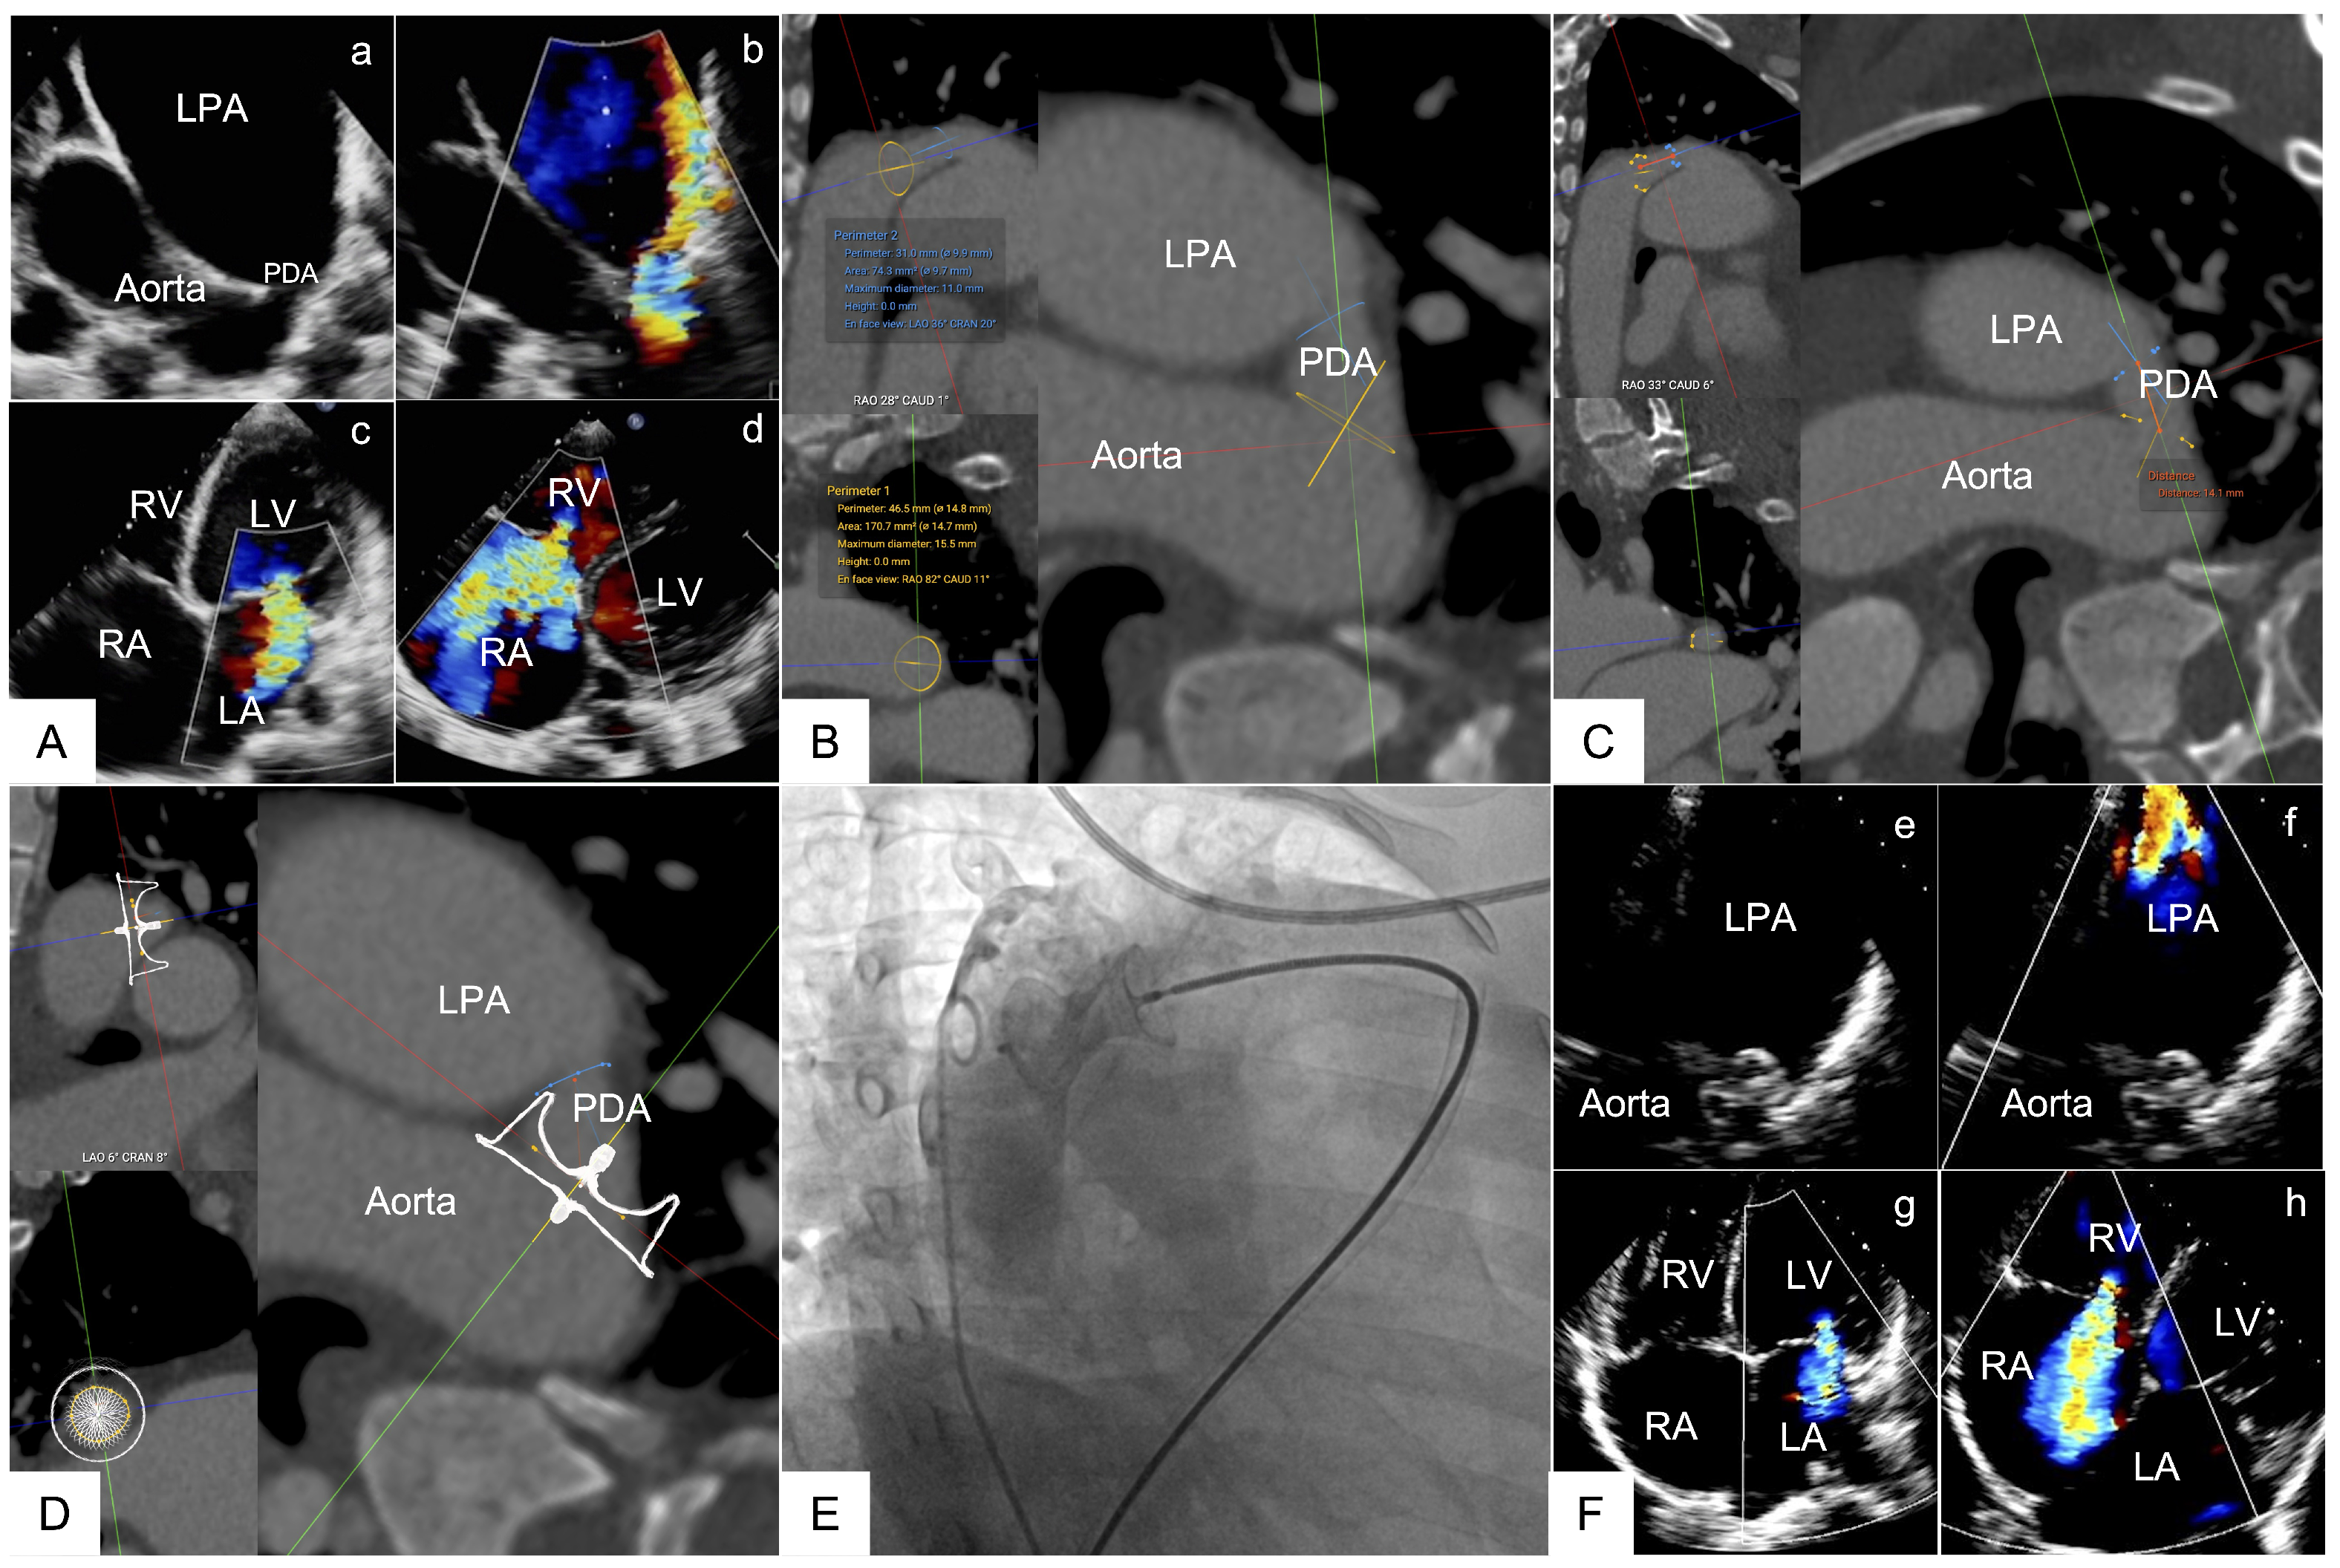

| PDA Occluder (n = 4) | Disc to AAM | 4.06 ± 0.88 | 3.98 ± 1.90 | 2.45 ± 1.08 | 0.93 | 0.24 | −0.13 to +0.62 |